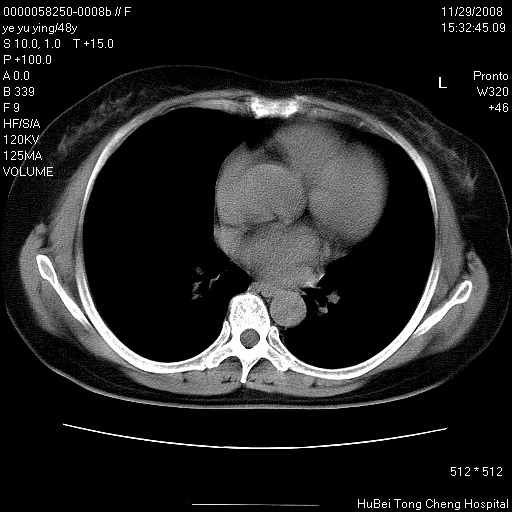

以下是引用zsl6918在2008-11-29 21:47:00的发言:[br]恶性肿瘤病史,转移瘤首先考虑。脂肪肝,胆囊结石。

以下是引用huenhao在2008-11-29 22:11:00的发言:[br]脂肪肝,胆囊结石。左肺病灶建议定期复查。

以下是引用liuyue在2008-11-30 5:44:00的发言:[br]1.左肺病变,首先考虑感染性病变,转移待排;建议治疗后复查。[br]2.肝脏密度普遍减低,考虑与化疗有关。[br]3.胆囊结石.